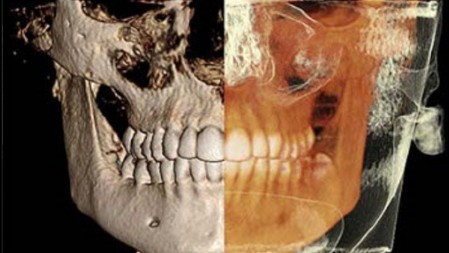

TC Cone Beam 3D (CBCT)

Con il termine TC Cone Beam (CBCT), si intende una macchina capace di scansionare le arcate dentali del paziente attraverso l’emissione di una dose molto bassa di raggi X fornendo immagini tridimensionali di altissima qualità delle ossa mascellari e dei denti. La tomografia Computerizzata Cone Beam 3D rappresenta pertanto il massimo raggiungibile nel campo della radiodiagnostica odontoiatrica.